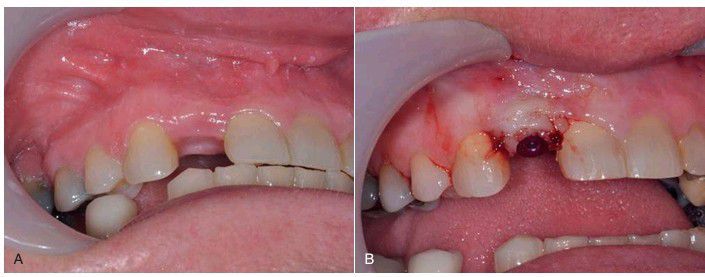

Second-stage exposure of implant with a small tissue flap. (A) Prior to uncovering. (B) After small flap elevation, the tissue is recontoured and sutured to maintain adequate keratinized tissue around the implant.